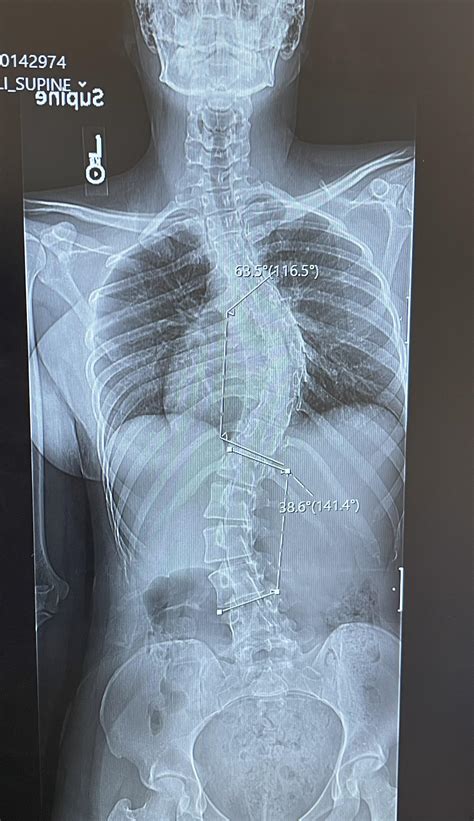

scoliosis spinal fusion rspinalfusion 900×1600 scoliosis spinal fusion rspinalfusion from www.reddit.com